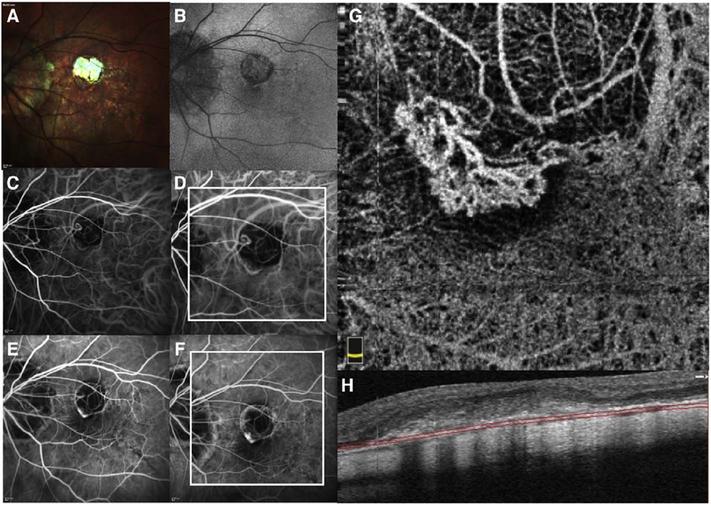

Optical coherence tomography (OCT) was one of the biggest advances in ophthalmic imaging. Building on that platform, OCT angiography (OCTA) provides depth resolved images of blood flow in the retina and choroid with levels of detail far exceeding that obtained with older forms of imaging. This new modality is challenging because of the need for new equipment and processing techniques, current limitations of imaging capability, and rapid advancements in both imaging and in our understanding of the imaging and applicable pathophysiology of the retina and choroid. These factors lead to a steep learning curve, even for those with a working understanding dye-based ocular angiography. All for a method of imaging that is a little more than 10 years old. This review begins with a historical account of the development of OCTA, and the methods used in OCTA, including signal processing, image generation, and display techniques. This forms the basis to understand what OCTA images show as well as how image artifacts arise. The anatomy and imaging of specific vascular layers of the eye are reviewed. The integration of OCTA in multimodal imaging in the evaluation of retinal vascular occlusive diseases, diabetic retinopathy, uveitis, inherited diseases, age-related macular degeneration, and disorders of the optic nerve is presented. OCTA is an exciting, disruptive technology. Its use is rapidly expanding in clinical practice as well as for research into the pathophysiology of diseases of the posterior pole.

光学相干断层扫描(OCT)是眼科成像领域的重大突破之一。在此基础上,OCT 血管造影术(OCTA)提供了视网膜和脉络膜血流的深度分辨图像,其细节水平远远超过了旧的成像方式。这种新的模式具有挑战性,因为需要新的设备和处理技术,目前成像能力的限制,以及成像和对视网膜和脉络膜成像及适用病理生理学的理解的快速发展。这些因素导致学习曲线陡峭,即使对于那些对基于染料的眼部血管造影术有一定了解的人来说也是如此。所有这些都是为了一种成像方法,它的历史还不到 10 年。这篇综述从 OCTA 的发展历史和 OCTA 中使用的方法开始,包括信号处理、图像生成和显示技术。这是理解 OCTA 图像显示内容以及图像伪影产生原因的基础。本文还回顾了眼部特定血管层的解剖结构和成像。介绍了 OCTA 在评估视网膜血管阻塞性疾病、糖尿病性视网膜病变、葡萄膜炎、遗传性疾病、年龄相关性黄斑变性和视神经疾病的多模态成像中的整合。OCTA 是一种令人兴奋的、颠覆性的技术。它在临床实践中的应用以及对后极部疾病病理生理学的研究中迅速扩展。